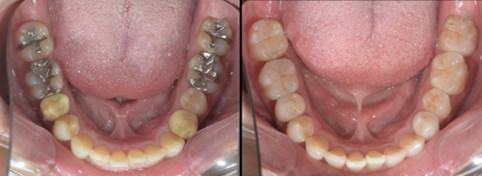

下の写真は保険診療と自由診療の差です。天然の歯を模倣して、虫歯になりにくいダイレクトボンディングは小規模の虫歯治療の最も優秀な選択肢です。